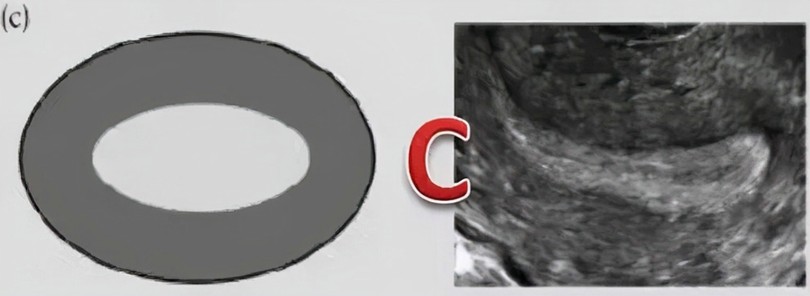

最后就是C型内膜了,内膜厚度增长到了10-14mm,C型内膜为整个子宫内膜表现为均一的强回声,三线不清晰。